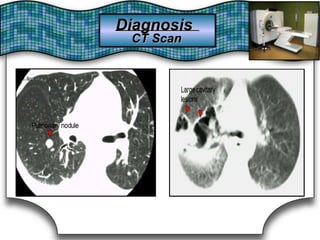

Advantages:Advantages:

1)Tomography is valuable in selected cases1)Tomography is valuable in selected cases to betterto better show theshow the

presencepresence

of lung cavities, solid masses,solid masses, and mediastinaland mediastinal & hilar& hilar LDN.LDN.of lung cavities,

2)Its2)Its complementary use with FOB givescomplementary use with FOB gives a greatera greater positive yield ofpositive yield of

pathology & is usefuluseful for excluding malignancy in high-risk patients.for excluding malignancy in high-risk patients.pathology & is

3)Allows3)Allows application of specialapplication of special imaging techniques:imaging techniques: e.g.,e.g.,

HRCT (1-3mm thickness section) →BronchiectasisHRCT (1-3mm thickness section) →Bronchiectasis

Spiral CT with pulmonary angiography →PESpiral CT with pulmonary angiography → PE